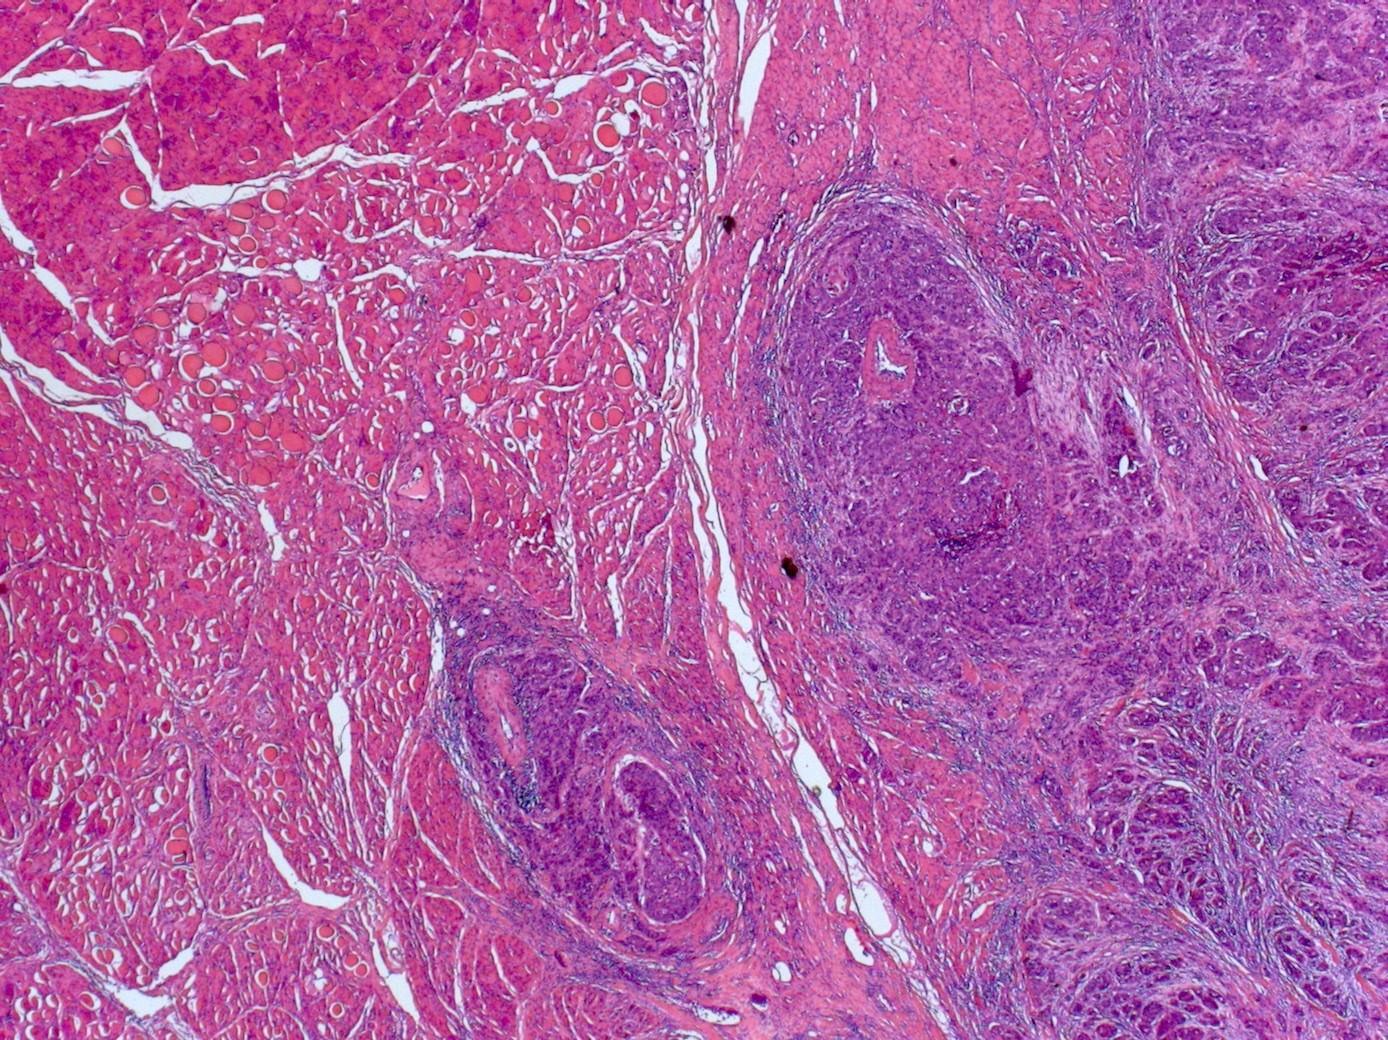

Histological grading

 For all cancer sites general principle in pathology that poorer differentiation associated with worse outcome

Poorly differentiated / basaloid SCC

Poorly differentiated basaloid SCC

Oral cavity / hypopharynx / larynx

 HPV negative and poorer prognosis than conventional SCC

Oropharyngeal

If HPV associated, radiosensitive and much better prognosis

Basaloid squamous cell carcinoma of upper aerodigestive tract: a single squamous cell carcinoma subtype of two distinct entities hiding under one histologic pattern. Woolgar et al Eur Arch Otolaryngol 2011